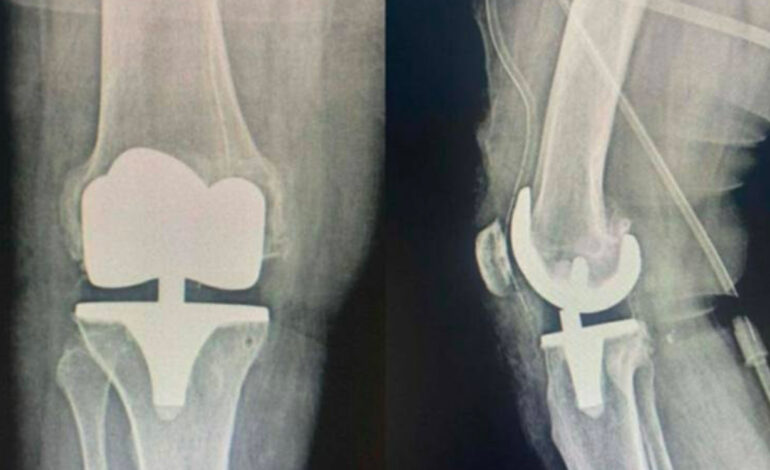

L’équipe de chirurgie orthopédique de l’Hôpital régional de Jendouba a récemment réalisé avec succès une opération de pose d’une prothèse totale du genou chez un patient souffrant d’une arthrose avancée de l’articulation. L’intervention s’est déroulée sous la supervision du docteur Seifeddine Mahjoubi.

Selon un communiqué publié par la Direction régionale de la santé de Jendouba, cette opération figure parmi les interventions les plus délicates en chirurgie orthopédique. Elle a été réalisée en étroite coordination avec l’équipe du service d’anesthésie et de réanimation, permettant son déroulement dans des conditions optimales et son aboutissement avec succès.